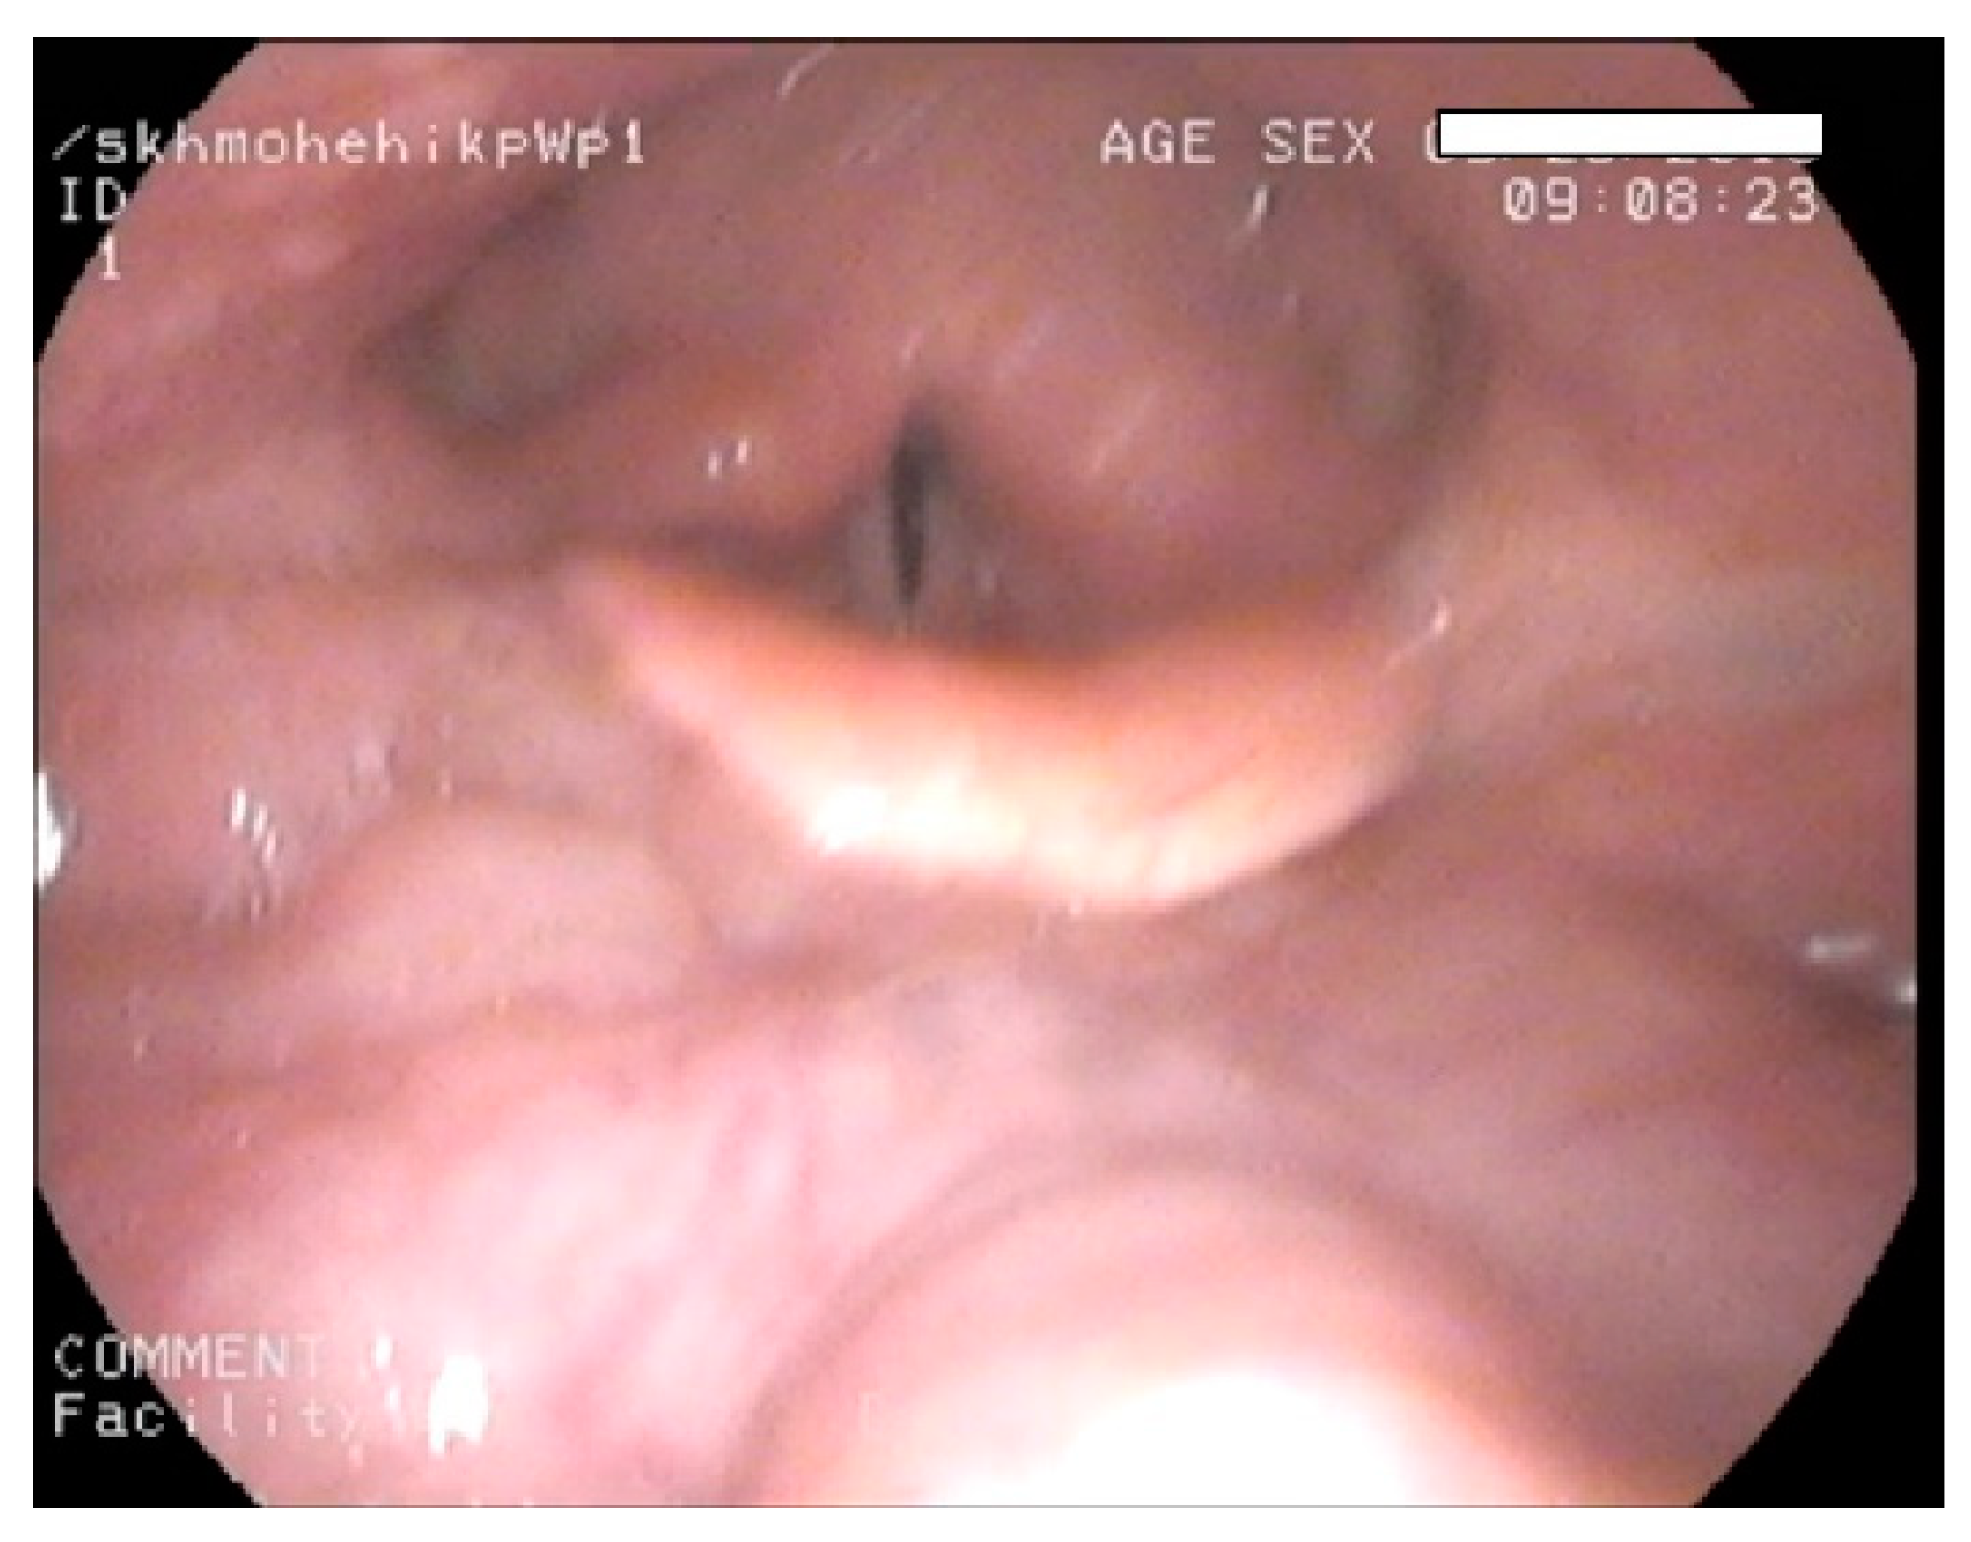

- Gadepalli, C.; Tol, G.; Yadthore, S.; Sharma, R.; Jovanovic, A.; Palmer, J.; Stepien, K.M. Nasendoscopy findings in adult patients with mucopolysaccharidosis: A tertiary UK centre experience. Mol. Genet. Metab. 2020, 129, S59–S60. [Google Scholar] [CrossRef]